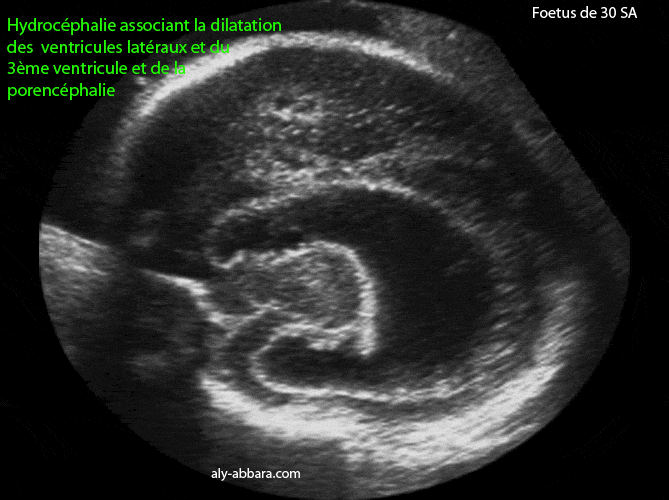

Hydrocéphalie et porencéphalie

Foetus âgé de 30 SA

Image échographique montrant, sur un coupe para-sagittale puis sur une coupe para-sagittale et oblique du cerveau fœtal, une hydrocéphalie associant la dilatation des ventricules latéraux et le 3ème ventricule avec une porencéphalie sous forme d'une zone hypo-échogène, à contour irrégulier, situé dans le lobe frontal du cerveau et mesurant 11 x 17 mm de diamètre..